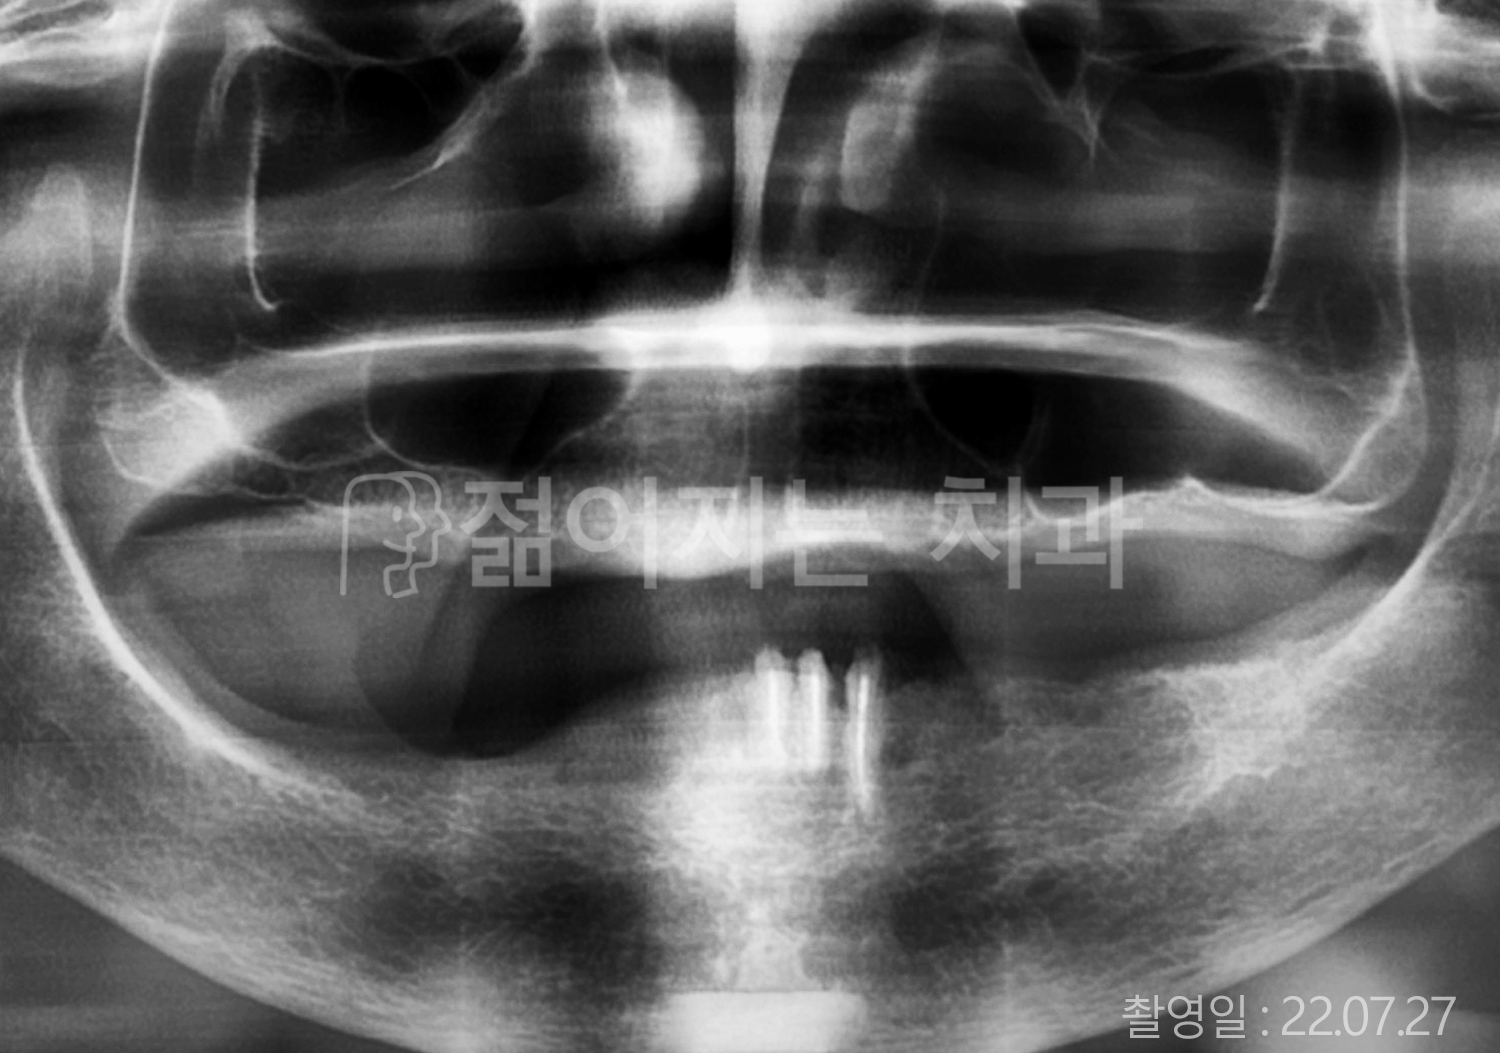

• 80대 전체치아 10개 이상 임플란트

• 60대 고혈압, 당뇨, 고지혈증 전체치아 10개 이상 임플란트

• 60대 전체치아 10개 이상 임플란트

• 60대 고혈압, 고지혈증 전체치아 10개 이상 임플란트

• 50대 고혈압, 당뇨, 고지혈증 전체치아 10개 이상 임플란트

• 70대 골다골증, 파킨스병 전체치아 10개 이상 임플란트

• 40대 전체치아 10개 이상 임플란트

• 60대 골다골증 전체치아 10개 이상 임플란트

• 40대 고혈압 전체치아 10개 이상 임플란트

• 50대 전체치아 10개 이상 임플란트

• 70대 전체치아 10개 이상 임플란트